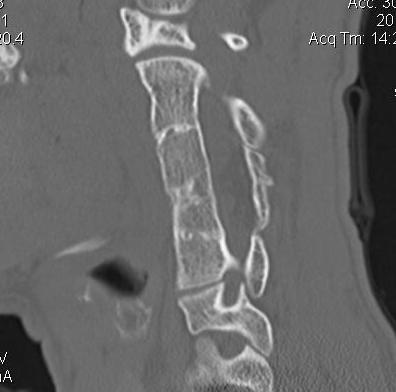

CT scan

Body fusion / block vertebrae

Hemivertebrae

Flattening & widening bodies

Hypoplasic discs

Cervical spina bifida